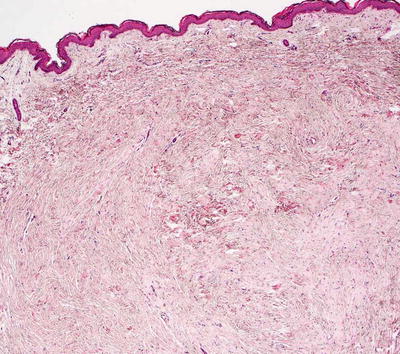

Collagenoma is the most common type of connective tissue nevus, and is characterized by a proliferation of thickened, haphazardly-oriented dense and coarse collagen bundles throughout the dermis [2] (Figs. 25.2 and 25.3). In some cases, electron microscopy has demonstrated increased number of myofibroblasts admixed with the dense collagen bundles [3]. A trichrome stain highlights the haphazard orientation of the dermal collagen bundles, and an elastic tissue stain may demonstrate fewer elastic tissue fibers within the lesional skin. In many cases, the diagnosis is subtle, and it is easiest to establish when lesional skin is compared with a biopsy taken from adjacent, clinically normal skin.

Fig. 25.2

A collagenoma is a type of connective tissue nevus that demonstrates a nodule of thickened collagen bundles haphazardly oriented with some bundles lying perpendicular to the surface of the skin